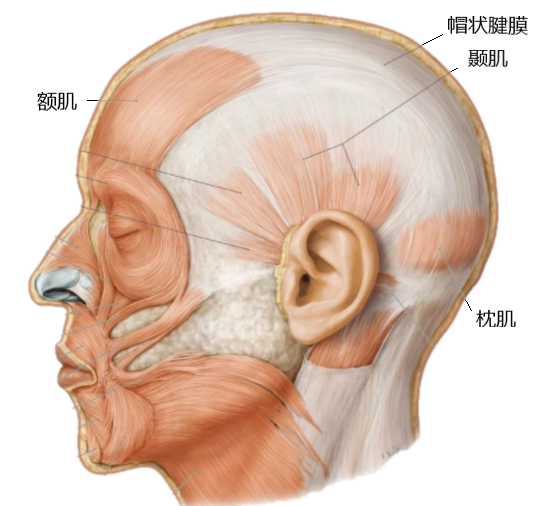

其中,颈浅筋膜向上连接帽状腱膜,其高张力使帽状腱膜紧张,牵拉额肌、颞肌、枕肌出现眼皮沉重、颞区胀痛及旋颈时颅颈运动不同步症状。颈深筋膜紧张,其内富含的本体感受器产生错误的感觉信息,空间定位受影响,从而出现头晕[1]。

验证性治疗时松解颈筋膜及帽状腱膜,颈深筋膜紧张解除,其内的本体觉感受器压力恢复正常,头晕症状随之消失。颈浅筋膜、帽状腱膜紧张解除,额肌、颞肌、枕肌等张力释放,眼皮沉重、颞区胀痛消失,头皮深浅筋膜之间滑动顺畅,颅颈运动不同步症状随之改善。寰枢关节半脱位亦是引起头晕症状的常见原因,但患者已行正骨治疗,查体时颈椎左右旋转正常、对称,且旋颈试验未引出头晕,知其与现有症状无明显关联,暂无需处理。

帽状腱膜:位于颅顶,紧贴骨膜,是头皮的第三层,为连结头部表浅肌肉的巨大肌腱。其前连额肌,后连枕肌,两侧连于颞肌。在前部移行为表浅肌肉腱膜系统及颈阔肌,在后部移行为附着于项韧带的颈部浅筋膜。

耳后区域由颈丛的耳大神经、枕小神经支配。枕部和后颈部由颈神经后支发出的枕大神经支配。帽状腱膜与深筋膜经深层脂肪组织分离,该组织是无脂肪细胞的薄层疏松结缔组织,为头部深浅筋膜之间的滑动创造条件,有助于头皮移动。当帽状腱膜紧张时,两层筋膜之间滑动迟滞,出现颅颈运动不同步的感觉。